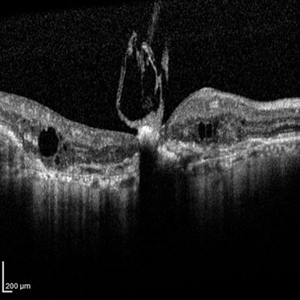

Best Disease Best DiseaseMar 9 2013 by Hamid Ahmadieh, MD OCT of the left eye of a 49-year-old man with decreased VA due to advanced Best disease. Photographer: Soodabeh Fooladin, Negah Eye Center, Tehran Imaging device: Heidelberg Spectralis Condition/keywords: Best disease, optical coherence tomography (OCT)